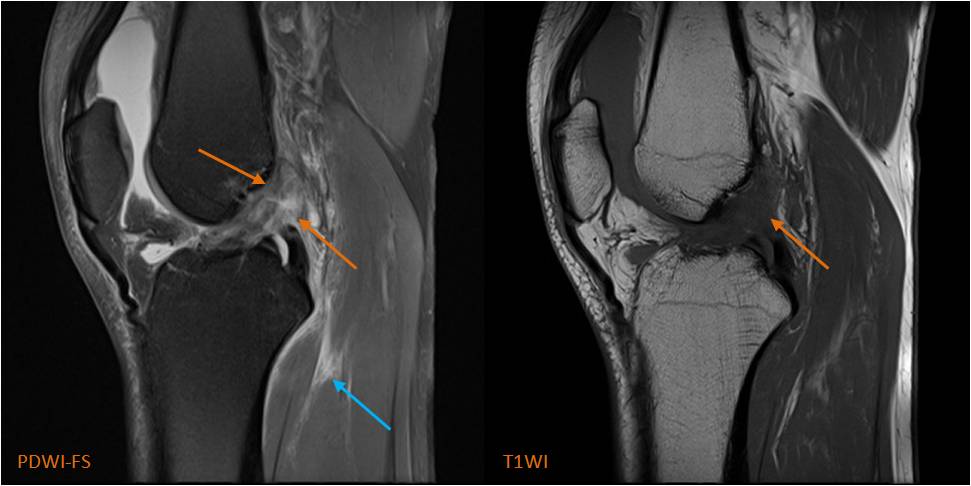

圖3 前交叉韌帶撕裂

男,26歲,膝關(guān)節(jié)外傷疼痛2小時(shí)。MRI示:前交叉韌帶纖維束連續(xù)性中斷,走行扭曲、紊亂,信號增高(PDWI-FS,橙箭),邊界不清。另外腘肌肌腱、肌腹及肌間隙損傷、積液(PDWI-FS,藍(lán)箭)。